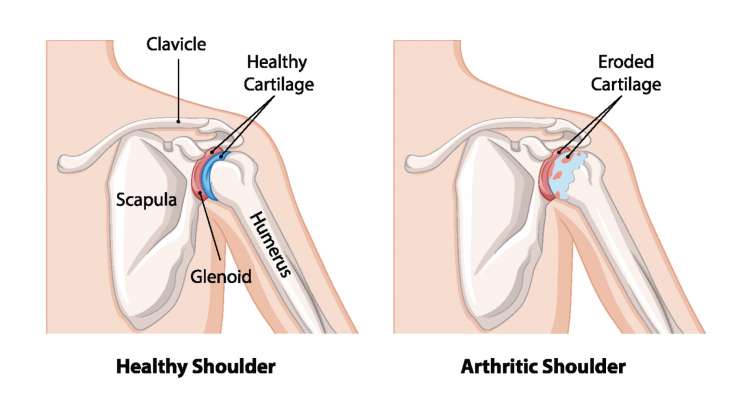

артроз акромиально-ключичного сустава

Артроз ACG описывает износ хряща в акромиально-ключичном суставе, который профессор, доктор медицины Франк Мартечшлегер лечит консервативно или путем оперативного расширения суставной щели в зависимости от степени выраженности, чтобы длительно облегчить боль и воспаление.

остеоартроз плечевого сустава

Профессор, доктор медицины Франк Мартечшлегер лечит артроз плечевого сустава (оартроз) в зависимости от стадии заболевания с помощью консервативных методов или с использованием современных протезов плечевого сустава, чтобы облегчить боль и восстановить подвижность надолго.